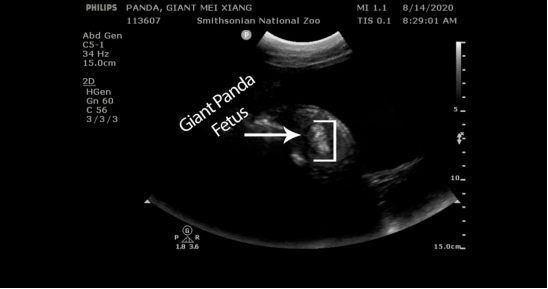

上周,位于华盛顿的美国国家动物园宣布,他们在14日早上为大熊猫美香进行了超声波检查,图像清楚地拍到了看起来像是胎儿的物体。动物园首席兽医Don Neiffer表示,甚至可能是两个胎儿。

美国国家动物园公布了美香的超声检查图像,疑似发现胎儿。(图片来源:美国国家动物园官网)